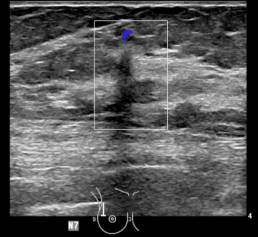

Femme de 74 ans avec antécédents familiaux de cancer du sein chez deux tantes maternelles (80 ans). Mammographie de dépistage : nouvelle petite masse spiculée de 0,6 cm dans le quadrant supérieur droit, qui persiste sur les vues de compression. MammoScreen : masse notée sur les vues CC et MLO avec un score de 6. Échographie : masse vasculaire de taille 0,6 x 0,5 x 0,7 cm. La lésion est molle sous élastographie, ce qui abaisse le niveau de supicion. Biopsie guidée par ultrasons : Carcinome micro invasif avec DCIS; ER/PR + Her2 -. Ki-67 modérée 11%.

*Cas de la pratique de Weinstein Imaging Associates, Danielle Sharek, M.D.